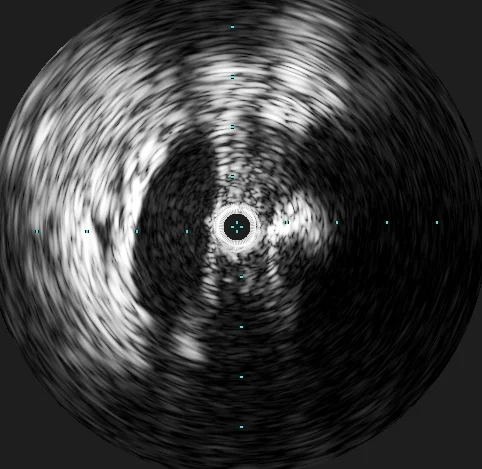

Post-lysis image 3

Intravascular ultrasound (IVUS) was performed, which demonstrated the presence of a severe stenosis of the left common iliac vein due to mass effect from the crossing right common iliac artery. This finding is diagnostic of a May-Thurner lesion, which was the underlying anatomic abnormality predisposing this young patient to an extensive DVT.